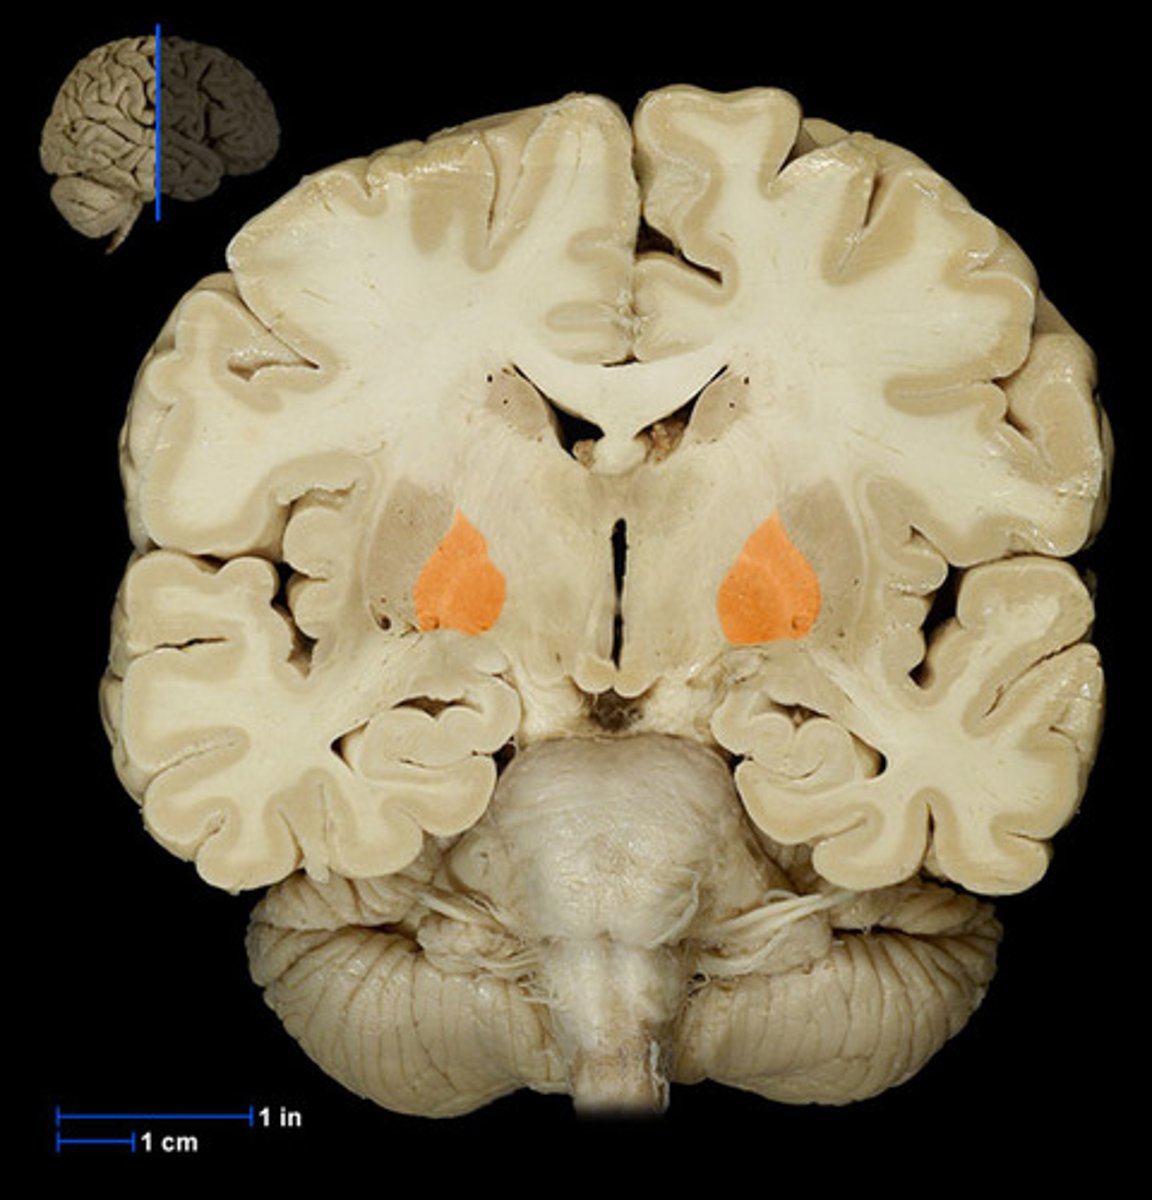

amygdala

rounded shape located medially in the temporal lobe. Appears with the hypothalamus, more rostral than the hippocampus. Plays a role in emotion.

hippocampus

the region of the brain more caudal than the amygdala, snail appearance medial in the temporal lobe. Appears with the thalamus+third ventricle. plays a role in memory.